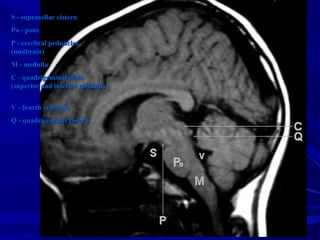

S - suprasellar cisternS - suprasellar cistern

Po - ponsPo - pons

P - cerebral pedunclesP - cerebral peduncles

(midbrain)(midbrain)

M - medullaM - medulla

C - quadrigeminal plateC - quadrigeminal plate

(superior and inferior colliculi)(superior and inferior colliculi)

V - fourth ventricleV - fourth ventricle

Q - quadrigeminal cisternQ - quadrigeminal cistern